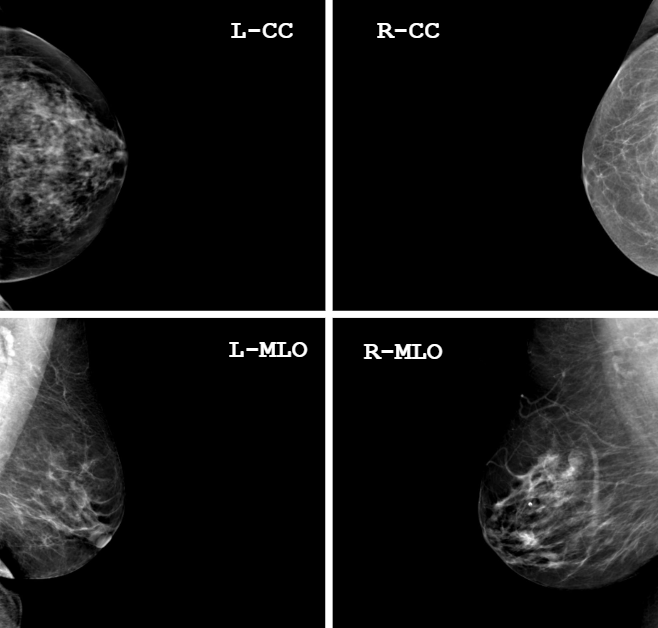

4-Views

Multiple Views

Study-Level Input (4 Views)